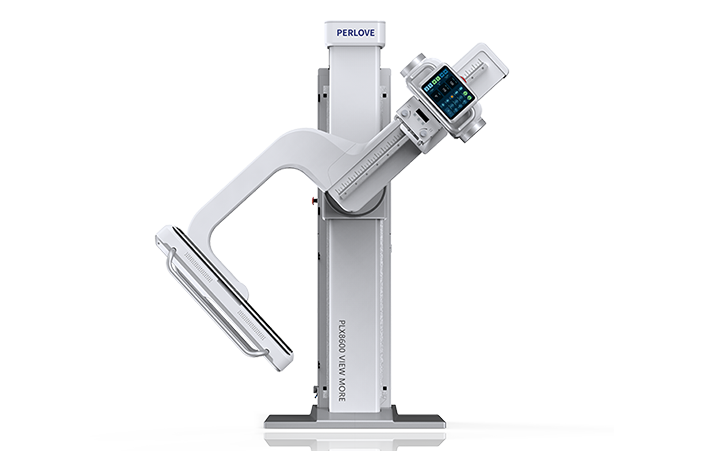

PLX8600

大视野平板动态DR

一板成像 岂止于大 PLX8600

支持全脊柱摄影、双下肢摄影、脊髓造影、复杂创伤、人工关节置换、关节损伤的修复重建等大视野临床应用

17"*34"有效视野,一次成像不拼接。相较于多张摄影再软件拼接的DR设备,PLX8600解决了拼接图像存在密度不均匀,拼接处图像配准和放大效应等问题,给临床带来了大视野影像解决方案,可一次性覆盖全脊柱或双下肢影像。

除常规静态摄影外,PLX8600大平板具备动态透视和点片功能,透视采集功能可支持大视野、多角度的可视化观察。通过可视化的动态影像,配合点片功能,能够很好的观察复杂部位病灶,有效的抓取关键帧,降低患者多次摄片的概率。如:全脊柱状态评估、长骨关节活动度、下肢静脉造影瓣膜功能评估、消化道功能评估、脊髓造影等更多大视野临床应用。

高功率大热容,为持久工作保驾护航。不管是摄影模式还是透视模式,均能保持长时间连续工作,无需预约,随到随拍。